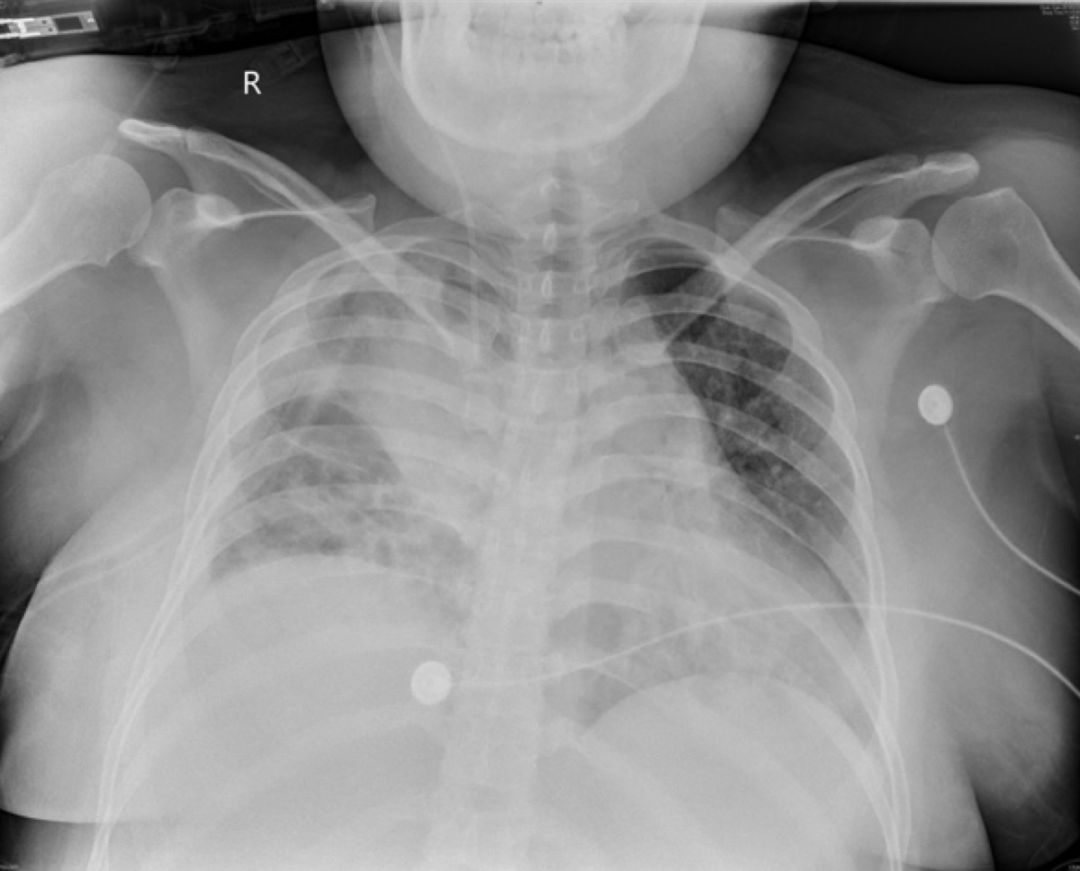

5-16胸片

5-17胸部LDCT

2019-5-21胸片:

2019-05-23床旁胸片:

本例患者的胸部CT主要表现为两肺相对弥漫分布的怪异的气囊和结节,气囊为薄壁,以中上肺分布为主,沿支气管血管束分布,符合LCH细胞沿支气管分布的特点,并且有可能会引起支气管阻塞,类似活瓣样的作用,因此囊腔的形状怪异。胸腔镜术后的CT表现,可能是局部阻塞牵拉引起疱的加重,也可能是胸膜粘连后局限性的气胸的表现。